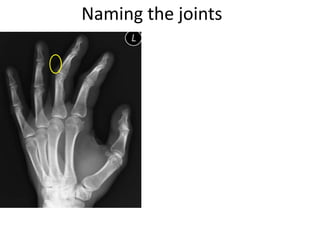

- Naming the bones, joints, tendons, nerves and skin landmarks of the hand and wrist.